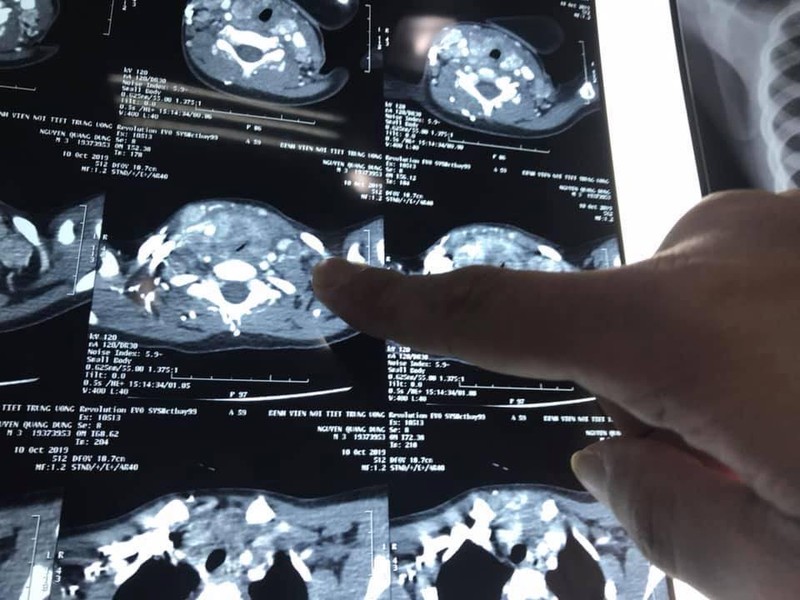

PGS.TS Trần Ngọc Lương - Giám đốc Bệnh viện Nội tiết Trung ương - nhận định, bé D. là trường hợp mắc ung thư tuyến giáp nhỏ tuổi nhất được phát hiện tại Bệnh viện. Ung thư đã di căn nhiều ở hạch cổ 2 bên của D., còn khối u tuyến giáp phát triển lớn chèn ép khí quản gây khó thở.

Ảnh chụp CT khối u của bé D.

Bên cạnh đó, do mức độ di căn lan rộng vào dây thần kinh, tĩnh mạch cảnh và khí quản, khối u gây đè bẹp khí quản nên quá trình gây mê cho bé D. rất khó khăn. Ngoài ra, việc sử dụng liều lượng thuốc cùng cần được cân nhắc kỹ lưõng.